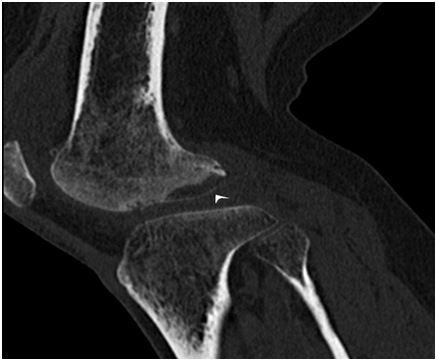

Figure 1 In the coronal fat-suppressed proton-weighted MR image (Figure 1A), subchondral cresenteric hyperintense signal (arrowhead), edema in the femur lateral condyle (arrow) and subchondral hypointense signal changes (arrowhead) in the T1-weighted MR image (Figure 1B) are observed.